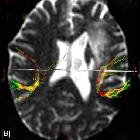

importance of fMRI and DTI in the presurgical planning of multicentric low-grade gliomas: a case report.. Axial FA colour-mapping images (A-D). The tumours, located at the right temporal and left frontotemporal regions, are visualized as a well-circumscribed bluish area, which is characteristic of low fractional anisotropy.

importance of fMRI and DTI in the presurgical planning of multicentric low-grade gliomas: a case report.. DTI tractography images (A-C) demonstrating the right and left arcuate fasiculli. The left one is not invaded but slightly displaced, while the right one is completely unaffected by the tumour.